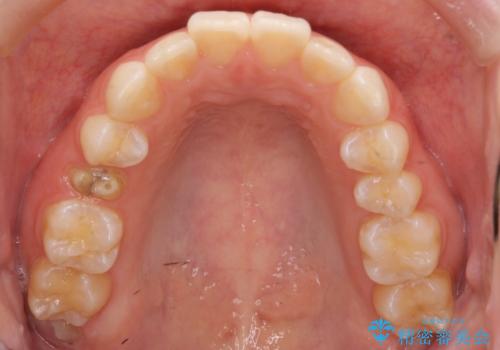

- 前歯のがたつきを治したいとのことでした。歯を抜かずにできる範囲で引っ込めたいとのことでした。

歯列の側方拡大(横に広げる)と、エナメル質の削合で並べました。

右上4番目の被せ物の治療については以下で紹介しています。